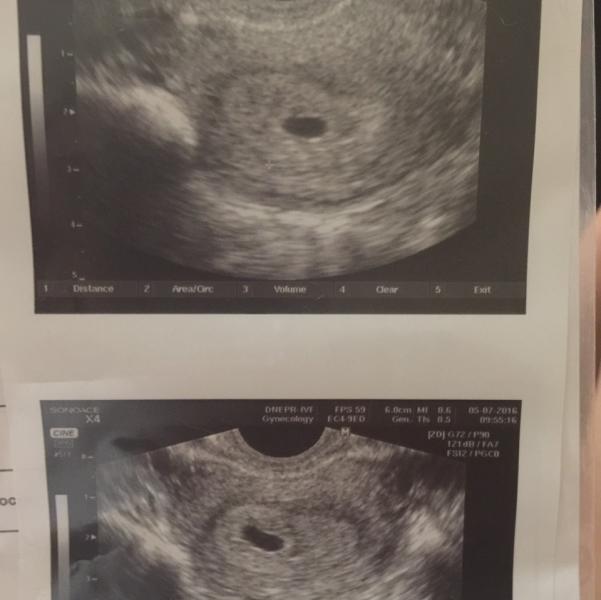

Сегодня были на узи , все отлично , эндометрий хороший , плодное яйцо хорошо видно , соответствует сроку как и по мес и по хгч !!!! Радости нет предела 😍😍😍😍😍😍😍

@annaom, ужи делала сегодня ))) последние м были 28.05.16 , цикл 28 дней ... Я не считала какой день задержки ... Если по мес считать то 5 недель и 3 дня